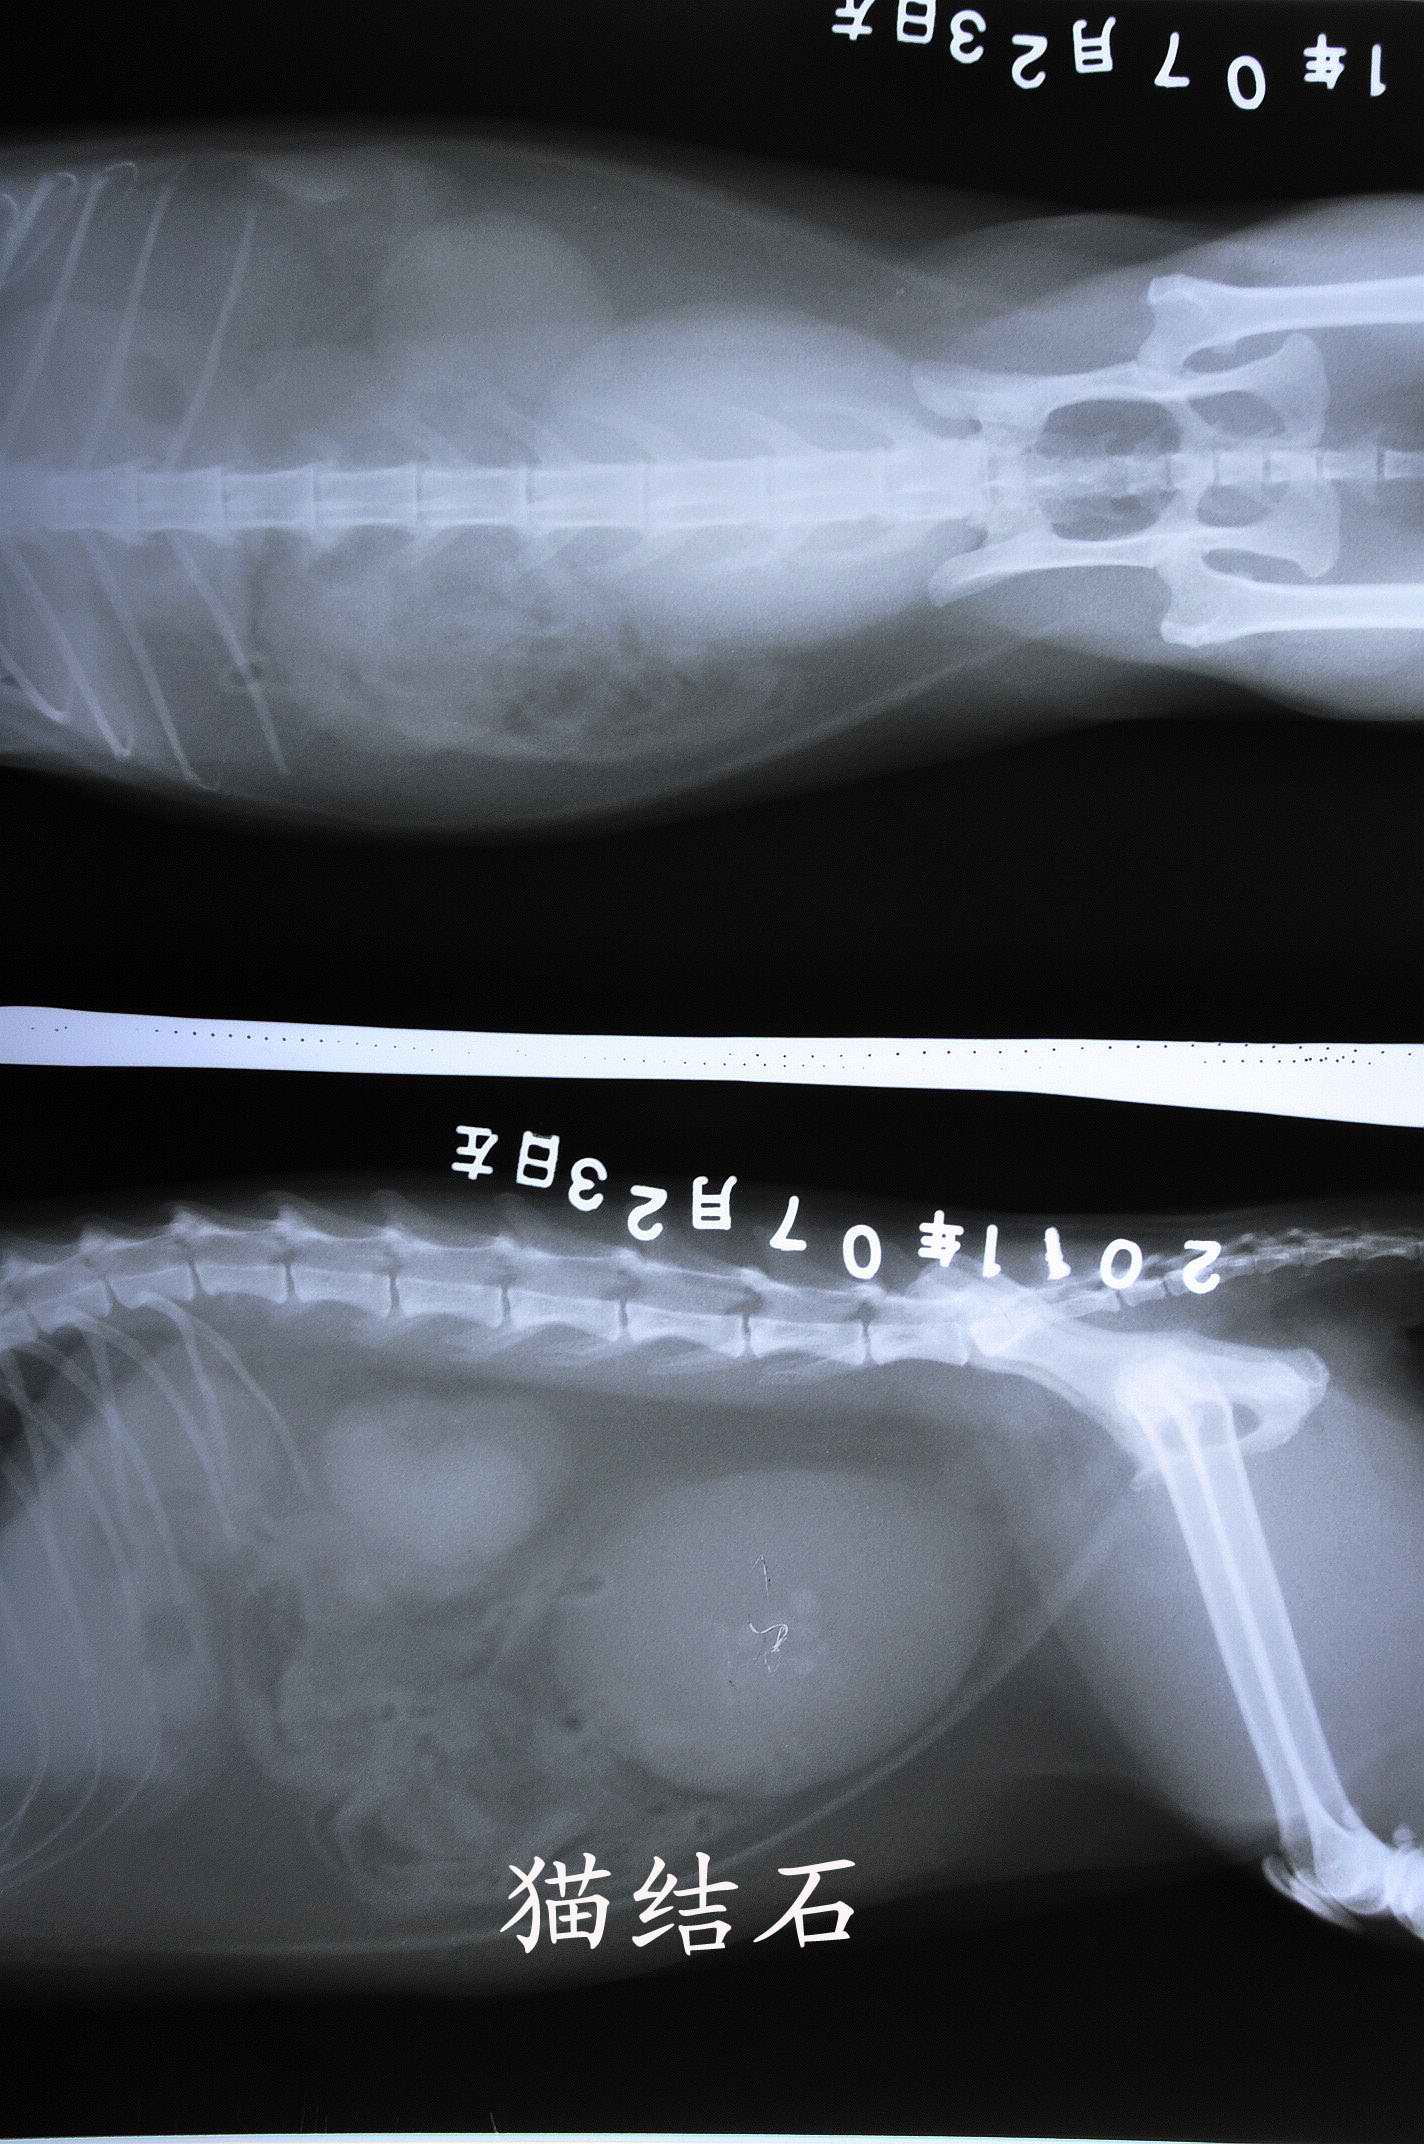

近有客户想要了解 下宠物X光机拍片的突显,以下使用我公司生产的宠物X光机拍摄的照片。 如果您需要采购宠物X光机。可以致电:0536-8322186或18953679166! 上一篇:上一篇:拍片机成像系统点片方案有哪些 下一篇:下一篇:如何区分CR拍片机和DR拍片机